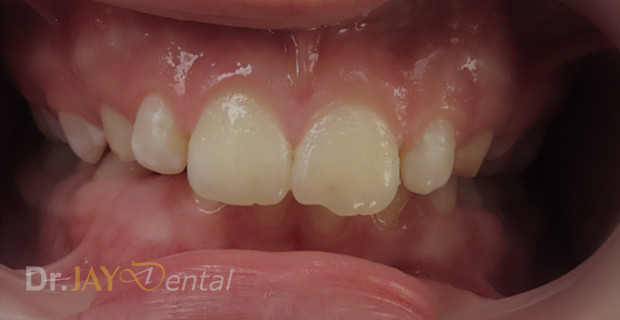

CASE 8

Patient had open bite and severe mouth breathing . At our office , patient went through myofunctional therapy , expansion of upper and lower jaw and aligning of teeth . No extractions needed and orthodontics was focused on airway, correcting habits and giving importance to the holistic health of patient. Patient’s mom extremely happy with the result.

Before

After